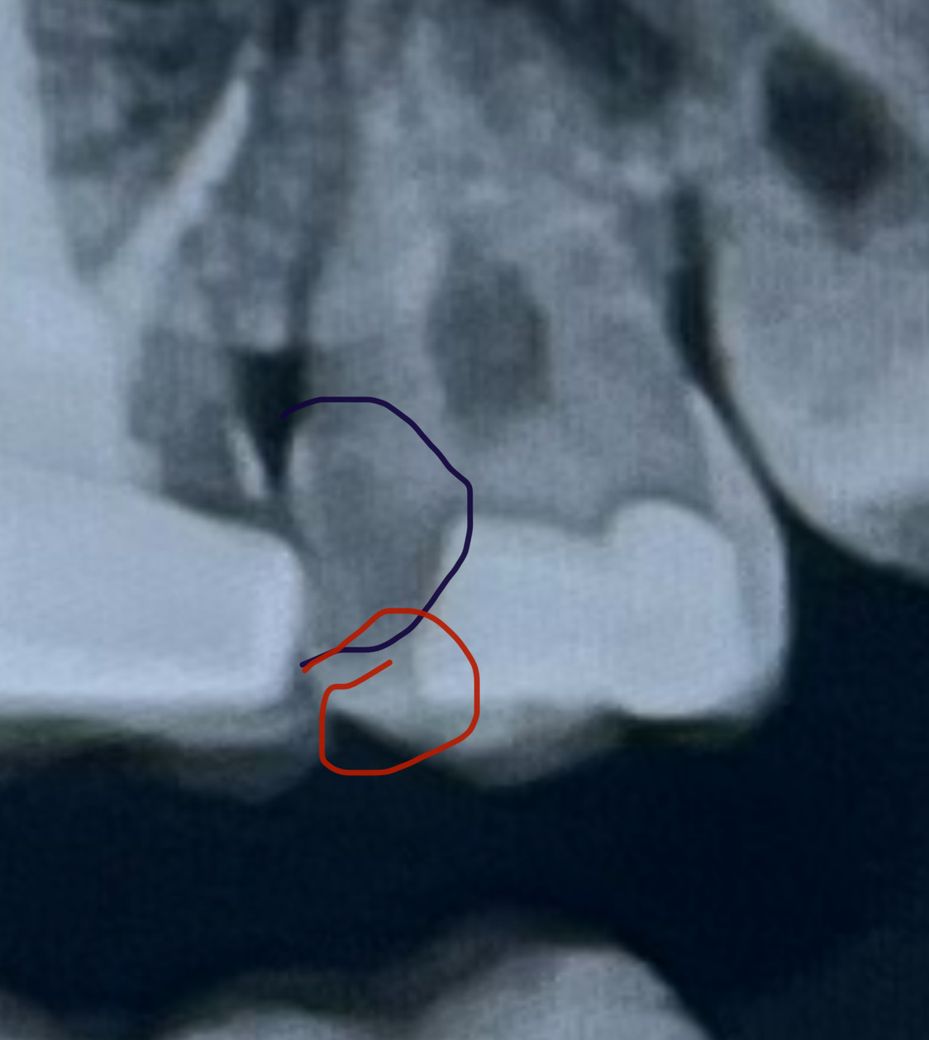

지금 빨간 부분으로 되어 있는 곳은 구멍이 혀로 만졌을 때 눌려지고 음식물도 안으로 들어가서 식후 바로 치실을 해주지 않으면 불편한데 내부에도 구멍이 뚫려 있을까요 사진은 올해 초에 찍은 건데 치아에 큰통증은 없어요

네 겉으로 보이는 크기보다 안쪽은 넓고, 충치를 깨끗하게 파내려면 구멍이 엑스레이에서 보이는 구멍보다도 훨씬 커질 것입니다. 신경치료 여부는 충치와 아말감을 제거해보고 신경과의 거리를 고려해 결정하게 될 것이지만 어래된 아말감 밑으로 2차충치가 생긴 경우에는 신경치료를 하게 될 가능성이 높기는 합니다. 엑스레이 사진상에도 아말감 밑에 충치 또는 들뜸이 있는게 보입니다. 따라서 치료 시에 수은이 나오더라도 어쩔 수 없 치료를 해야하는 상황입니다. 그래도 아말감 수은에 대해서는 익히 알려져있기 때문에 아마 치과측에서도 아말감에사 나오는 수은 증기를 최소화하기 위해 고성능흡입기를 추가로 사용할 것이고, 아말감 덩어리가 떨어져나올 때마다 빼내드릴 것입니다. 환자분께서는 아말감가루를 삼키지 않도록 침이나 물을 삼키지 마시고 잘 머금고 계시면 됩니다.

참고로 이미 신경치료 후 크라운 씌우신 치아도 크라운 밑쪽으로 충치가 보이는데 엑스레이사진만으로는 확실하지 않으므로 정확한 것은 치과에 문의해보시길 바랍니다.